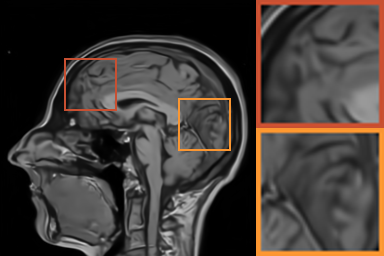

As shows in Fig. 1, at the first several iterations, the loss of is slightly larger than that of . Because the input is corrupted with severe artifacts, thus the role of data-driven module is significant at the first several steps. But as process goes on, repeated denoising operation in turn causes over-smoothing. While module can make up for it by incorporating model based knowledge. Though can improve the performance, it cannot ideally converge to a desired solution. The solid line indicates the superiority of Ours over other choices in both convergence rate and reconstruction accuracy. The execution time of , , and Ours is 4.4762s, 3.3240s, 6.2760s and 2.5225s, respectively. As expect, the proposed method provides a much faster reconstruction process. Thus we can verify that our framework has higher efficiency both in terms of theoretical convergence and practical execution time. The visualized results in Fig. 2 also verify that Ours has better performance than others.

First, we test on 25 T1-weighted MRI data using three different undersampling patterns with a fixed 10% sampling rate. Fig. 3 shows the quantitative results (PSNR). Our method performances best for all three cases and has stronger stability compared with the second best method on variance. As for the effect of sampling ratios variation, we use radial mask under 10%, 30% and 50% sampling rates with evaluation of RLNE and MSE. Fig. 4 shows that our method has the lowest reconstruction error for all sampling rates. For more intuitive comparison, we illustrate the reconstruction error in term of pixels in Fig. 5. We also offer the qualitative comparison in Fig. 6. Visualized results demonstrate our method has better performance in both artifacts removing and details restoration. Time consuming is also considered. We compare our method with others on the 25 T1-weighted data using Radial mask with 10% and 50% sampling rate. Notice that ADMM-Net and ours are tested on GPU for the incorporation of deep architecture. Tab. 1 shows that our method provides an efficient reconstruction process and comes to the fastest method among the state-of-the-art competitors.

To demonstrate the robustness of our approach, we first apply it on various MRI data including the chest, cardiac and renal (?). In Tab. 2, Our proposed framework gives the highest PSNR for all of the tree types of MR images. Fig. 7 visualizes the corresponding results for chest data. we can see that our approach prevails over others in detail restoration at the junction of blood vessels as well as noise removal in the background. Actually, our method has a stronger ability to handle slight noise because of the subprocess of learning based optimization with deep prior. To demonstrate that, we add Rician noise at level of 20 to 25 T1-weighted MRI and 25 T2-weighted MRI to generate the noisy data. As what is shown in Fig. 8, our method over leads all the competitors by a large margin when the input is corrupted with Rician noise.